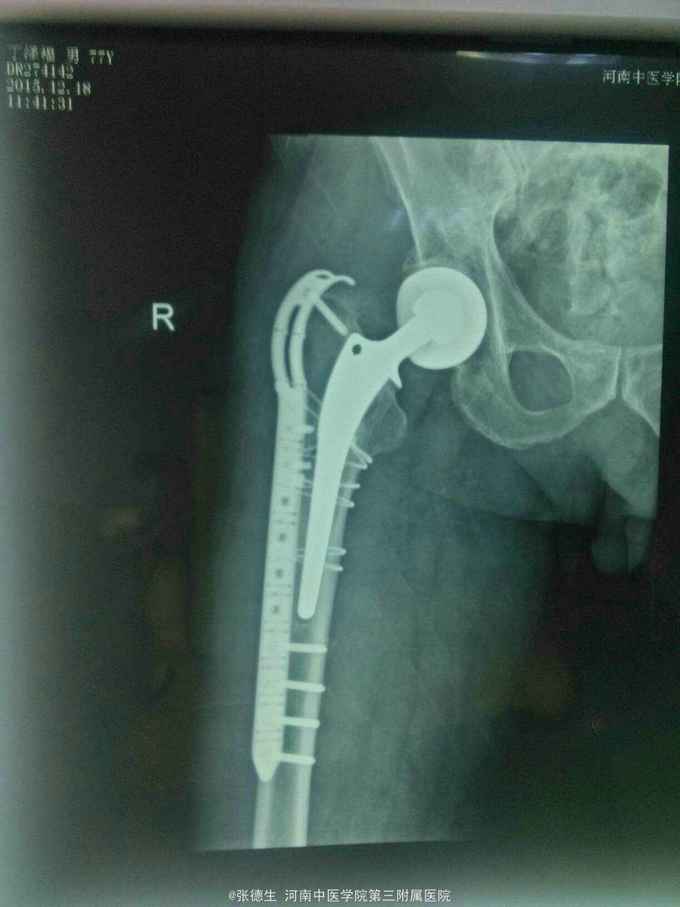

右股骨假体周围骨折 切开复位锁定板加扎带内固定术

假体周围骨折手术相对复杂,必要考虑假体是否松动或磨损,如果有要考虑假体翻修,翻修过程当中应考虑骨缺损等。本病例术前准备了全髋翻修,但术中发现假体完好,股骨柄与大小转子处无明显松动,即时给予复位锁定板加扎带固定。